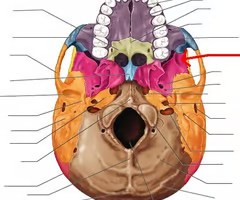

Palatine process of maxilla (helps form hard palate with palatine bones)

Palatine bones

Vomer

Occipital condyles (articulates with superior articular surfaces of atlas)

Foramen magnum (“big hole” for the spinal cord)

Jugular foramen (for internal jugular vein and nerves)

Carotid canal (for internal carotid artery)